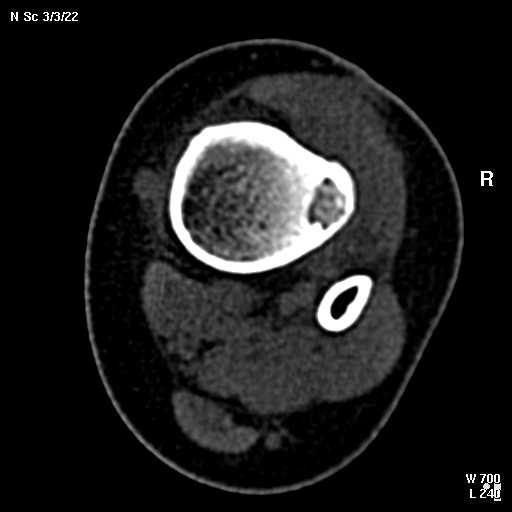

В обсуждении темы возникла необходимость дополнительных данных.

КТ изображения передаю на мой взгляд самые демонстративные. Их любезно записал коллега,

проводивший исследование в другом городе.